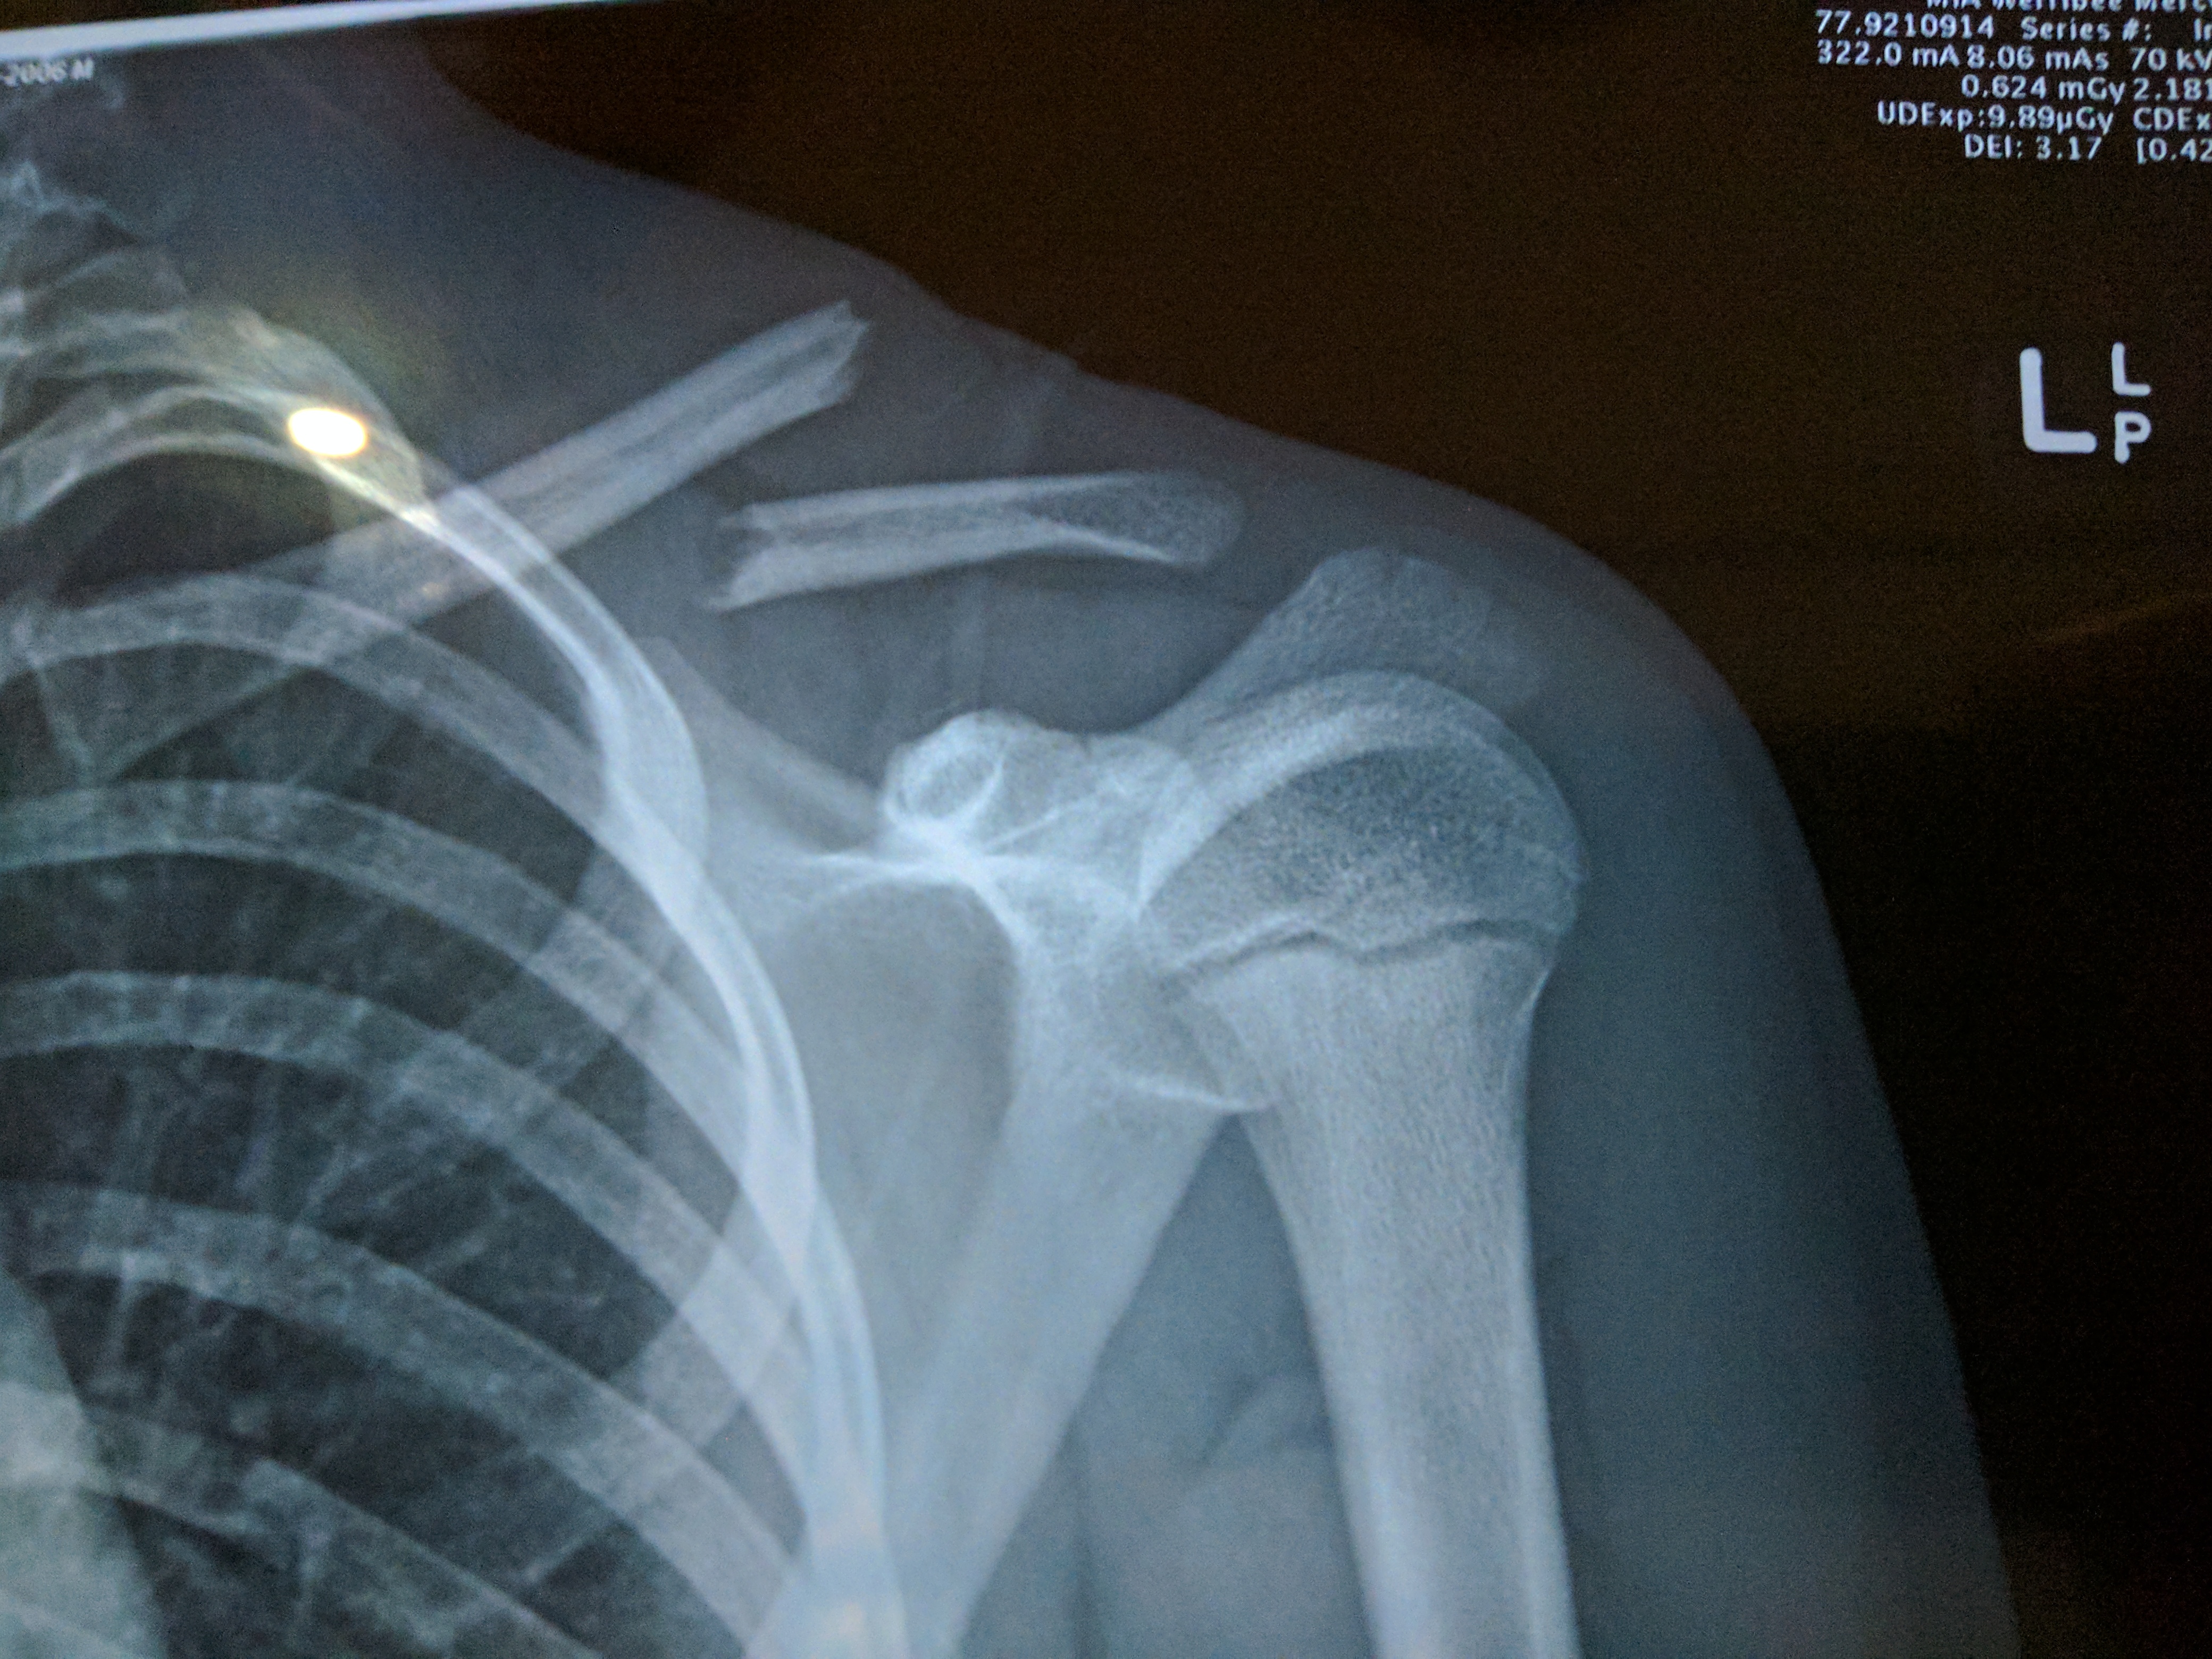

How do healthcare providers diagnose a broken collarbone? The diagnostic process typically involves:

- Physical examination: A healthcare provider will inspect the area for tenderness, swelling, and any open wounds.

- X-rays: These imaging tests reveal the location and severity of the fracture, as well as any joint involvement.

- CT scans: In some cases, more detailed images may be necessary to assess the extent of the injury.

What information can be gathered from these diagnostic tools? X-rays and CT scans help determine the fracture’s location, severity, and whether any joints are affected. This information is crucial for developing an appropriate treatment plan.

During the physical exam, a health care provider inspects the area for tenderness, swelling or an open wound. X-rays show where the break is, how bad it is and whether the joints are injured. A CT scan might give more-detailed images.